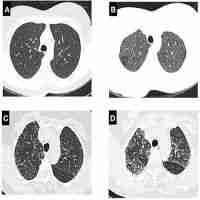

| Abstract | Hypersensitivity pneumonitis (HP) is one of the most common interstitial lung diseases (ILD), that presents unique challenges for a confident diagnosis and limited therapeutic options. The disease is triggered by exposure to a wide variety of inciting antigens in susceptible individuals which results in T-cell hyperactivation and bronchioloalveolar inflammation. However, the genetic risk and the pathogenic mechanisms remain incompletely elucidated. Revised diagnostic criteria have recently been proposed, recommending to classify the disease in fibrotic and non-fibrotic HP which has strong therapeutic and outcome consequences. Confident diagnosis depends on the presence of clinical features of ILD, identification of the antigen(s), typical images on high-resolution computed tomography (HRCT), characteristic histopathological features, and lymphocytosis in the bronchoalveolar lavage. However, identifying the source of antigen is usually challenging, and HRCT and histopathology are often heterogeneous and not typical, supporting the notion that diagnosis should include a multidisciplinary assessment. Antigen removal and treating the inflammatory process is crucial in the progression of the disease since chronic persistent inflammation seems to be one of the mechanisms leading to lung fibrotic remodeling. Fibrotic HP has a few therapeutic options but evidence of efficacy is still scanty. Deciphering the molecular pathobiology of HP will contribute to open new therapeutic avenues and will provide vital insights in the search for novel diagnostic and prognostic biomarkers. |